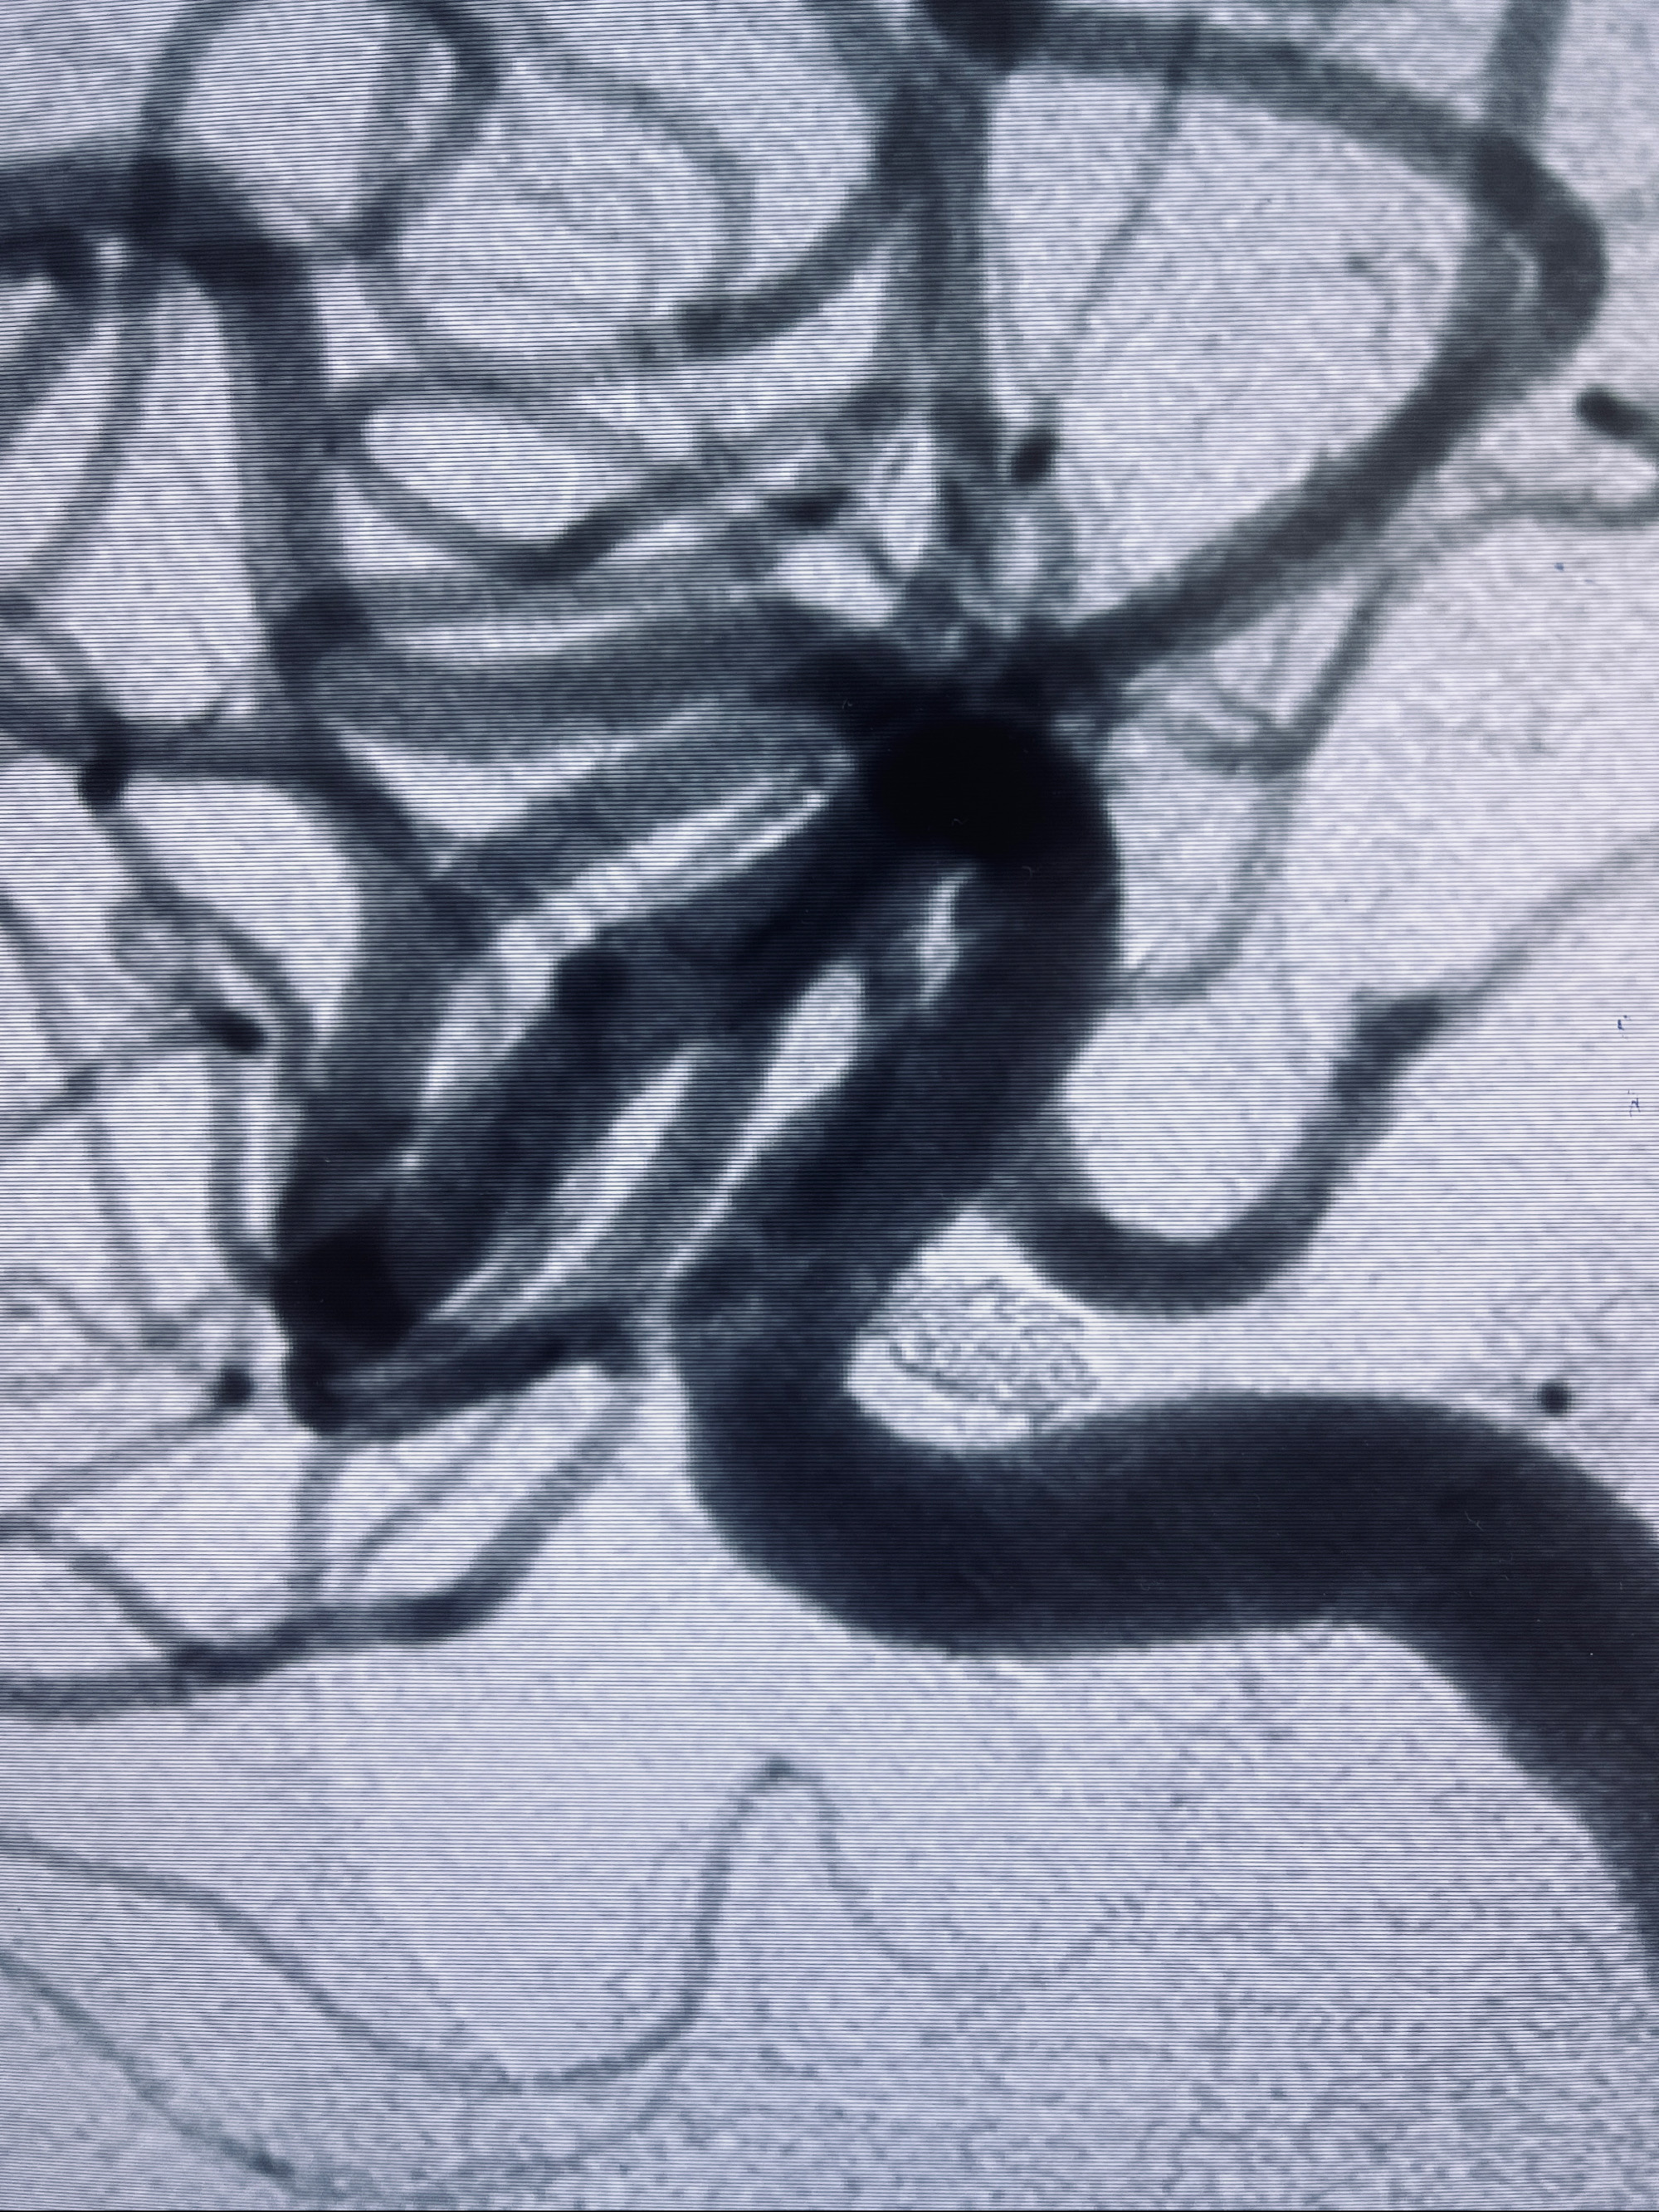

2022-09-29复查DSA

患者支架内血栓,给予阿司匹林+立普妥+依折麦布强化降脂干预